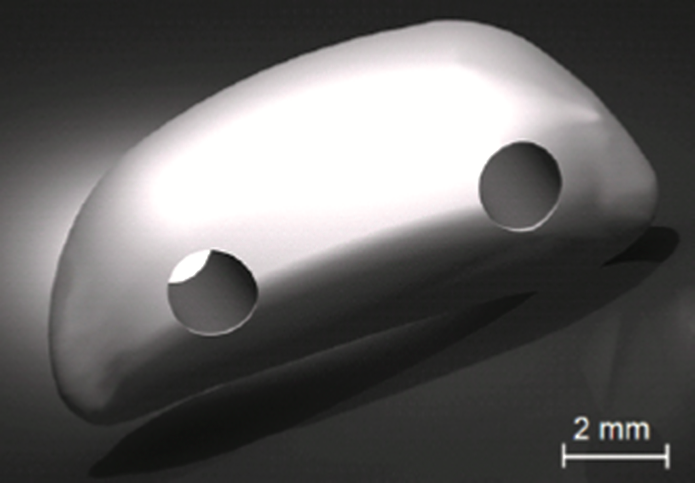

FDM printed patella pictured before implantation.

OIC built an artificial patella using FDM® technology, an additive manufacturing process that builds plastic parts layer-by-layer from CAD files, on its Stratasys® 3D printer using PC-ISO™ biocompatible polycarbonate (ISO 10993 USP Class VI). Physical testing was performed on the implant to validate its ability to provide the necessary mechanical strength. The implant was sterilized using ethylene oxide at 54°C (130°F) for one hour. During Oreo’s surgery, the implant was attached to the tendon and quadriceps using polypropylene sutures.